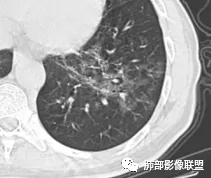

晚期:修复最终导致间质纤维化改变,双肺小叶间隔明显增厚,肺叶呈纤维状、条索状、网格状改变,支气管牵拉性扩张和蜂窝肺,HRCT病灶显示为碎石路征样改变,是本病的特征表现之一,该征象出现表示肺泡、肺间质同时受累,是病变进展的重要表现。肺气囊是肺孢子菌肺炎较常见的影像学特征,多见于晚期,多分布于肺上叶或肺周边, 也可发展到整个肺实质,其形成是由于肺实质的破坏。肺气肿可破裂引发自发性肺气胸、纵隔及皮下气肿。